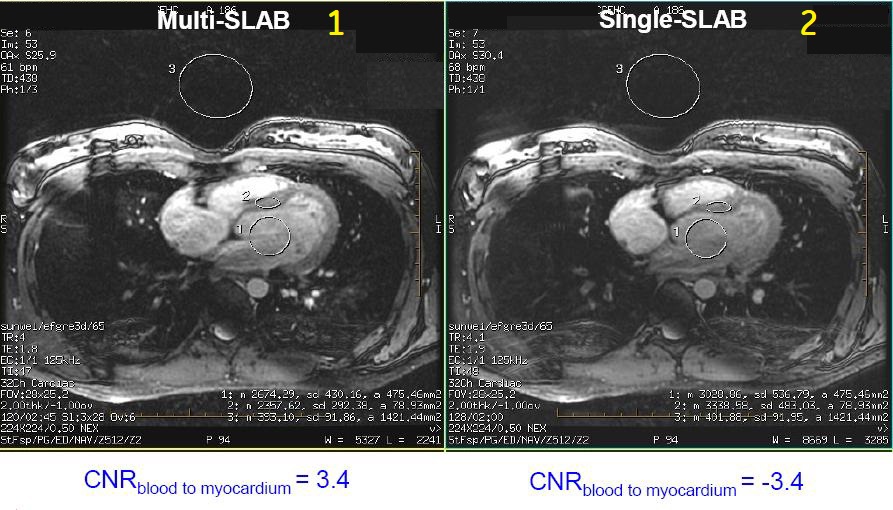

Figure 1. Slab comparison

Table 1. Image legend Callout Description 1 Multi-SLAB. Note the improved CNR between blood and myocardium. 2 Single-SLAB Footer CNR blood to myocardium = 3.4 - 1 NEX with center-outer k-space ordering for increase SNR.